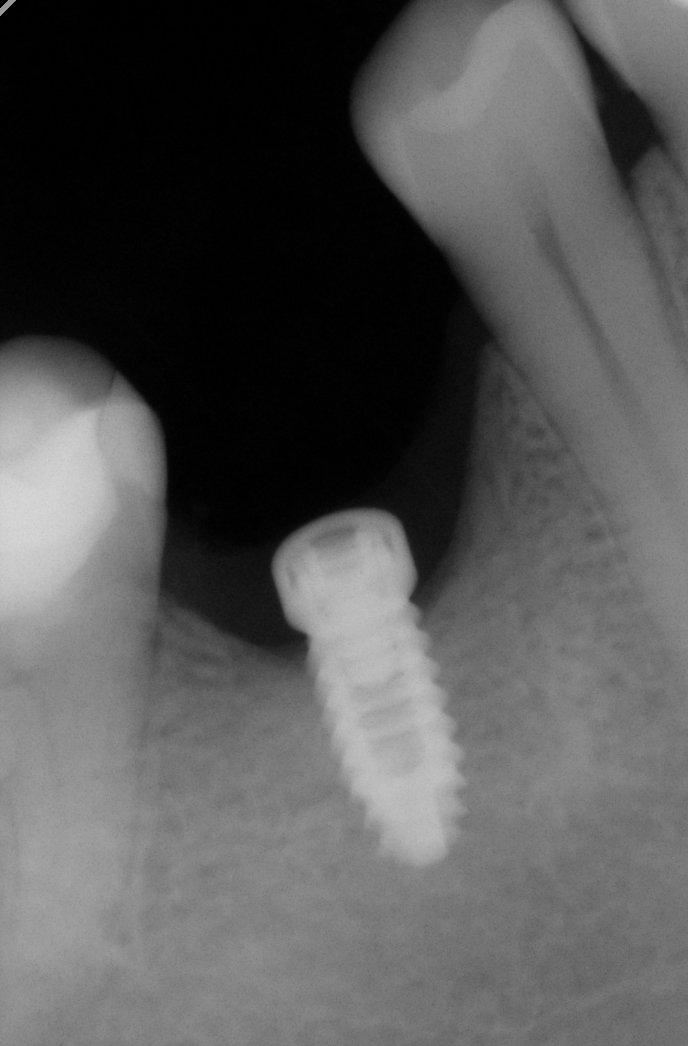

Buenas tardes, Necesitamos averiguar la marca del Implante en 46. Según nos dice el Paciente se lo puso en 2017. Muchas gracias. Un saludo.

Son implantes de conexión externa, y necesito saber qué tipo de pilares corresponde a estos implantes, gracias

Paciente Venezolano que tiene temporales y aun no ha ido a la consulta para iniciar tratamiento.